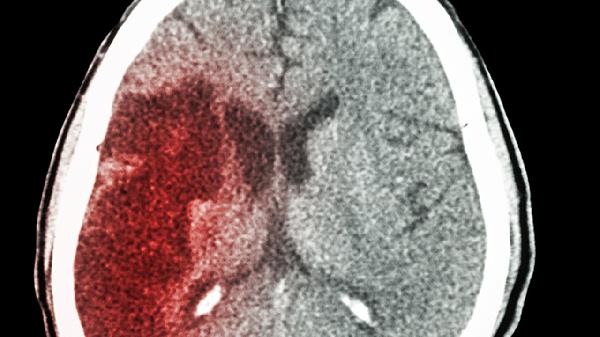

脑出血后遗症可通过康复训练、药物治疗、物理治疗、心理干预、手术治疗等方式改善。脑出血后遗症通常由神经功能缺损、脑组织损伤、代谢紊乱、心理障碍、并发症等因素引起。